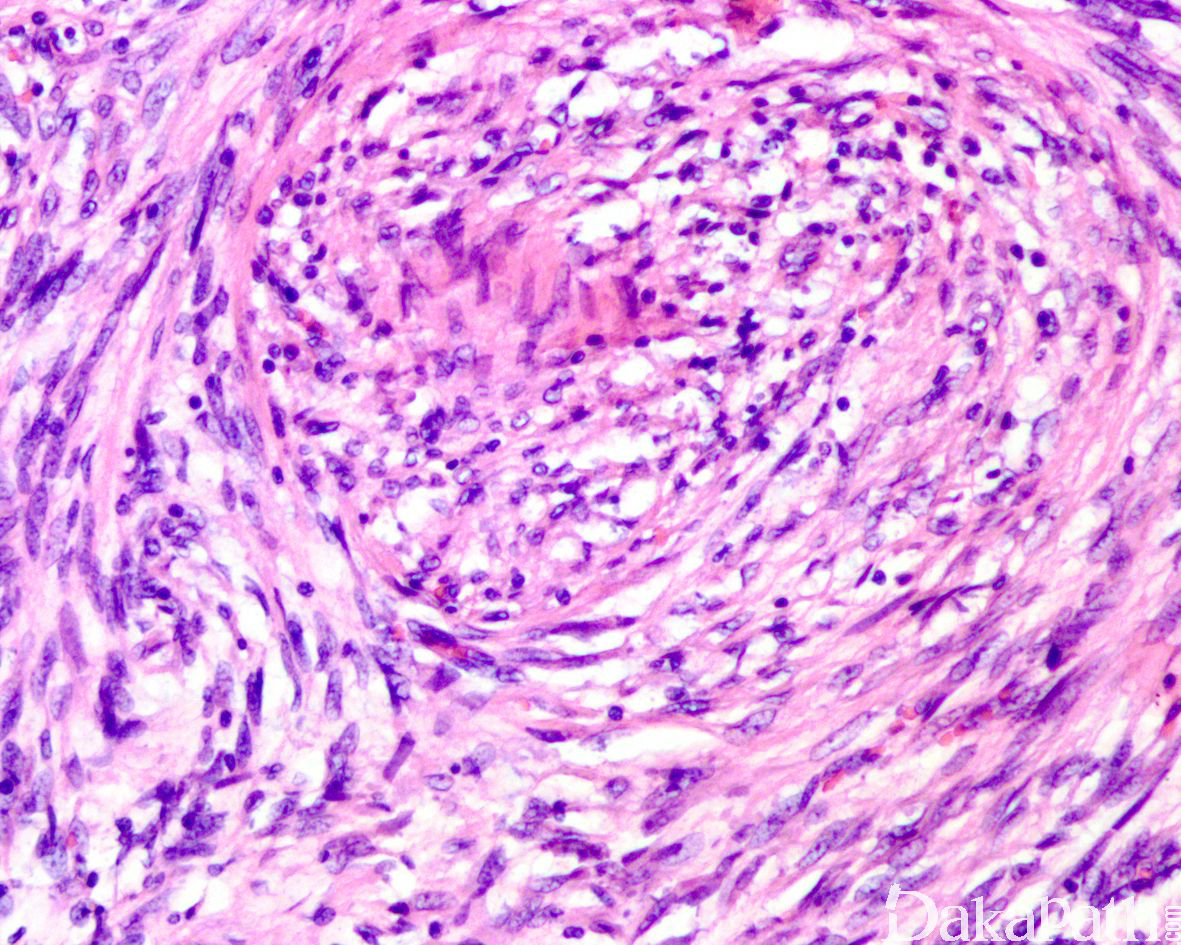

少数情况下,去分化成分可表现为低级别去分化组织学特征包括低度恶性纤维黏液肉瘤样、纤维瘤病样、炎性肌纤维母细胞瘤样以及孤立性纤维性肿瘤样等,低级别去分化成分瘤细胞以纤维母细胞样细胞为主,密度相对较低,间质较丰富,核异型性轻-中度,核分裂象< 5 个/10 HPF,罕见坏死。在后腹膜和腹部盆腔等部位的 DDLPS 可表现明显的间质黏液变性,特别是低级别 DDLPS,局部的黏液变性可导致稀疏的瘤细胞于血管周聚集从而类似于低级别黏液纤维肉瘤,而广泛的黏液变性导致局部的丛状小血管聚集和肺水肿样组织间隙使得 DDLPS 可能非常类似于黏液样脂肪肉瘤。另一少见而特殊的 DDLPS 特征为脑膜上皮样漩涡伴有化生性的骨形成,组织学上表现为低级别的梭形或胖梭形瘤细胞围绕中央小血管呈同心圆状或洋葱皮样排列,类似于脑膜瘤中常见的漩涡样结构,在漩涡的周围常见伴随的化生性骨形成。该组织学特征常出现在低级别去分化的 DDLPS 中,尽管罕见,但当其出现的时候具有高度的诊断提示作用。